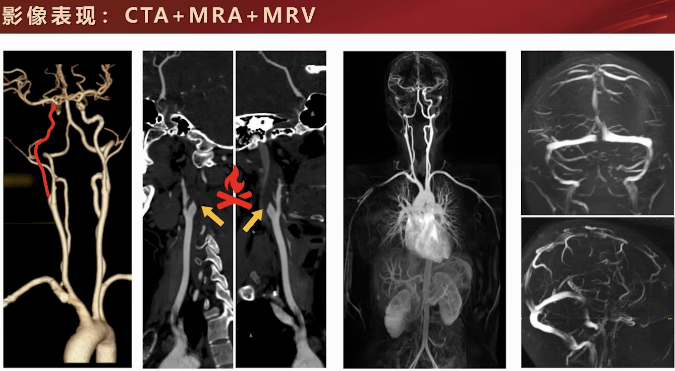

3) 影像学检查结果:神经内科开具头颅CT和磁共振检查。CT平扫发现右额颞交界部有低密度条状影;磁共振显示右额颞交界部T2等高信号、T1低信号、FLAIR明显高信号,考虑为急性期梗死灶。加扫SWI排除皮层下微出血或铁沉积。CMA和MRA显示右侧颈内动脉起始部缺损,三维重建呈火焰样尖角改变,全身MRA提示右侧颈内动脉闭塞,MRV无静脉异常或栓塞表现。

2) 病因分型与检查选择:缺血性脑卒中病因分型包括大血管型、心源性、其他原因(如血管炎、动脉夹层等)及不明原因性卒中。常规影像检查后,为明确病因及鉴别诊断,进一步对血管壁结构成像十分必要。因此,选择进行头颈一体化血管壁成像。

1) 成像表现与诊断依据:TOF-MRA显示右侧颈动脉闭塞,起始部狭窄,重建可见线样低信号影及尖角样片样改变。管壁成像T1平扫及增强可见螺旋样血管腔内改变、血管腔内T1加权像高信号,考虑为假腔内血栓或斑块内出血。增强后红色虚线区域有螺旋样上升线样结构,整体考虑为颈内动脉夹层。

3. 磁共振管壁成像的核心诊断价值:CTA等传统血管成像主要显示管腔狭窄或闭塞(如“火焰征”),但无法清晰显示血管壁的病理改变。磁共振管壁成像能直接显示夹层的特征性表现:T1WI上的壁内高信号血肿、内膜片,并能准确评估累及范围。该技术是鉴别动脉夹层与早发性动脉粥样硬化、血管炎等其他血管壁疾病的关键。